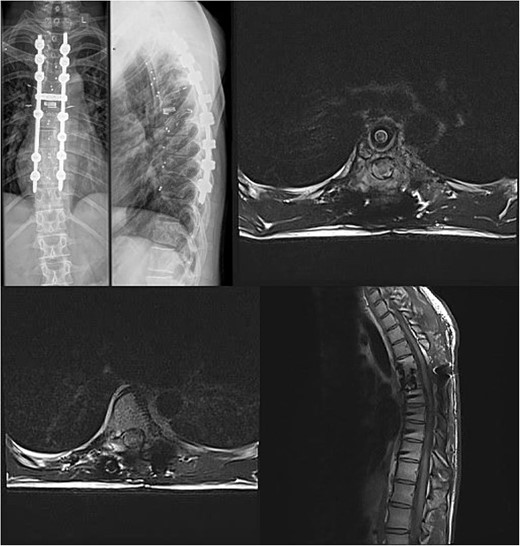

We decided to perform a revision total en bloc spondylectomy at Th6, along with resection of the Th8 pedicle and costovertebral joint, with a partial resection of the adjacent rib. Posterior spinal fixation from Th3 to Th10 was performed using radiolucent carbon screws, and the Th6 body was reconstructed using a radiolucent expandable cage (Figs 3 and 4). During the surgery, MEPs and SEPs were lost, with the patient waking up paraplegic (ASIA score B, VAS pain score 5). Immediate postoperative MRI showed no residual signs of thoracic spinal cord compression due to tumour or haemathoma (Fig. 5). The patient’s neurological status substantially improved the day after surgery, and thereafter, gradually improving over the next few days, allowing the patient to walk independently within 10 days (ASIA score D, VAS pain score 3). A multidisciplinary council decided against postoperative radiotherapy to avoid aggravating neurological symptoms by possibly causing additional damage to the myelopathic spinal cord. On the 11th postoperative day, the patient reported dyspnoea, and urgent CT angiography revealed peripheral pulmonary embolism, which was managed utilizing Deltaparine. Subsequent postoperative course was uneventful, leading to his discharge on the 15th postoperative day, ambulating independently using a walker. MRI follow-up was conducted 6 months postsurgery, followed by yearly checks. At the last follow-up, 2.5 years after the second surgery, there were no signs of tumour recurrence, and the patient exhibited no gait disturbance, back pain, or radiological signs of spinal instability (Fig. 6) (ASIA score E, VAS pain score 0).

Postoperative X-ray imaging immediately after surgery; anteroposterior view (left) and lateral view (right).

Immediate postoperative MRI showing no residual signs of thoracic spinal cord compression.